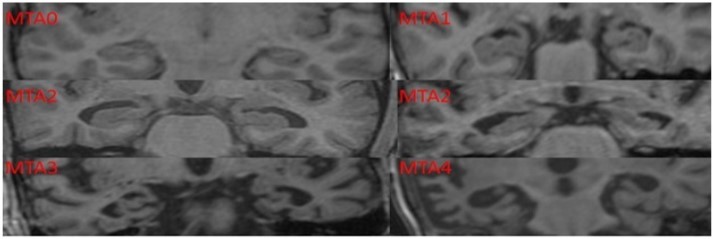

Scheltens Visual Rating of Medial Temporal Lobe Atrophy: The visual rating of MTLA was done using this scale5by obtaining T1 weighted coronal section image on MRI scan of the brain. This rating does not require any special radiological training and can be done easily using hard copies of T1 weighted coronal sections of the brain

MRI. It has a diagnostic accuracy of over 80% in diagnosing dementia of Alzheimer’s type (Table 1).

Table 1. Methodology of Scheltens Visual Rating for Medial Temporal Rating Scale| Scoring | Interpretation |

| 0 | No atrophy |

| 1 | Minimal atrophy |

| 2 | Mild atrophy |

| 3 | Moderate atrophy |

| 4 | Severe atrophy |

Radiology Protocol

MTLA was assessed using a template based on Scheltens Visual Rating Scale (Figure 1). MRI scans were done using 1.5 Tesla Magnetic Resonance (Megnatom Symphony 1.5T scanner). T1 weighted Coronal sections were used for rating MTLA.

Figure 1.Scheltens Visual Rating Scale used in the current study to assess the medial temporal lobe atrophy rating scores.